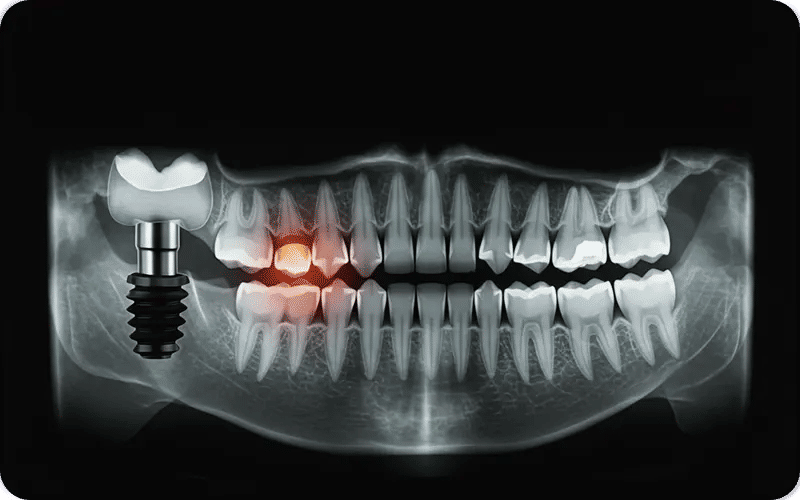

5. Visible issues in scans or images (bad dental implants xray / bad dental implants pictures): X-rays or clinical photos may reveal bone loss, poor placement, or structural failure not visible to the naked eye.

- Discover the Cause: Get X-rays or scans to assess bone integration and implant alignment.